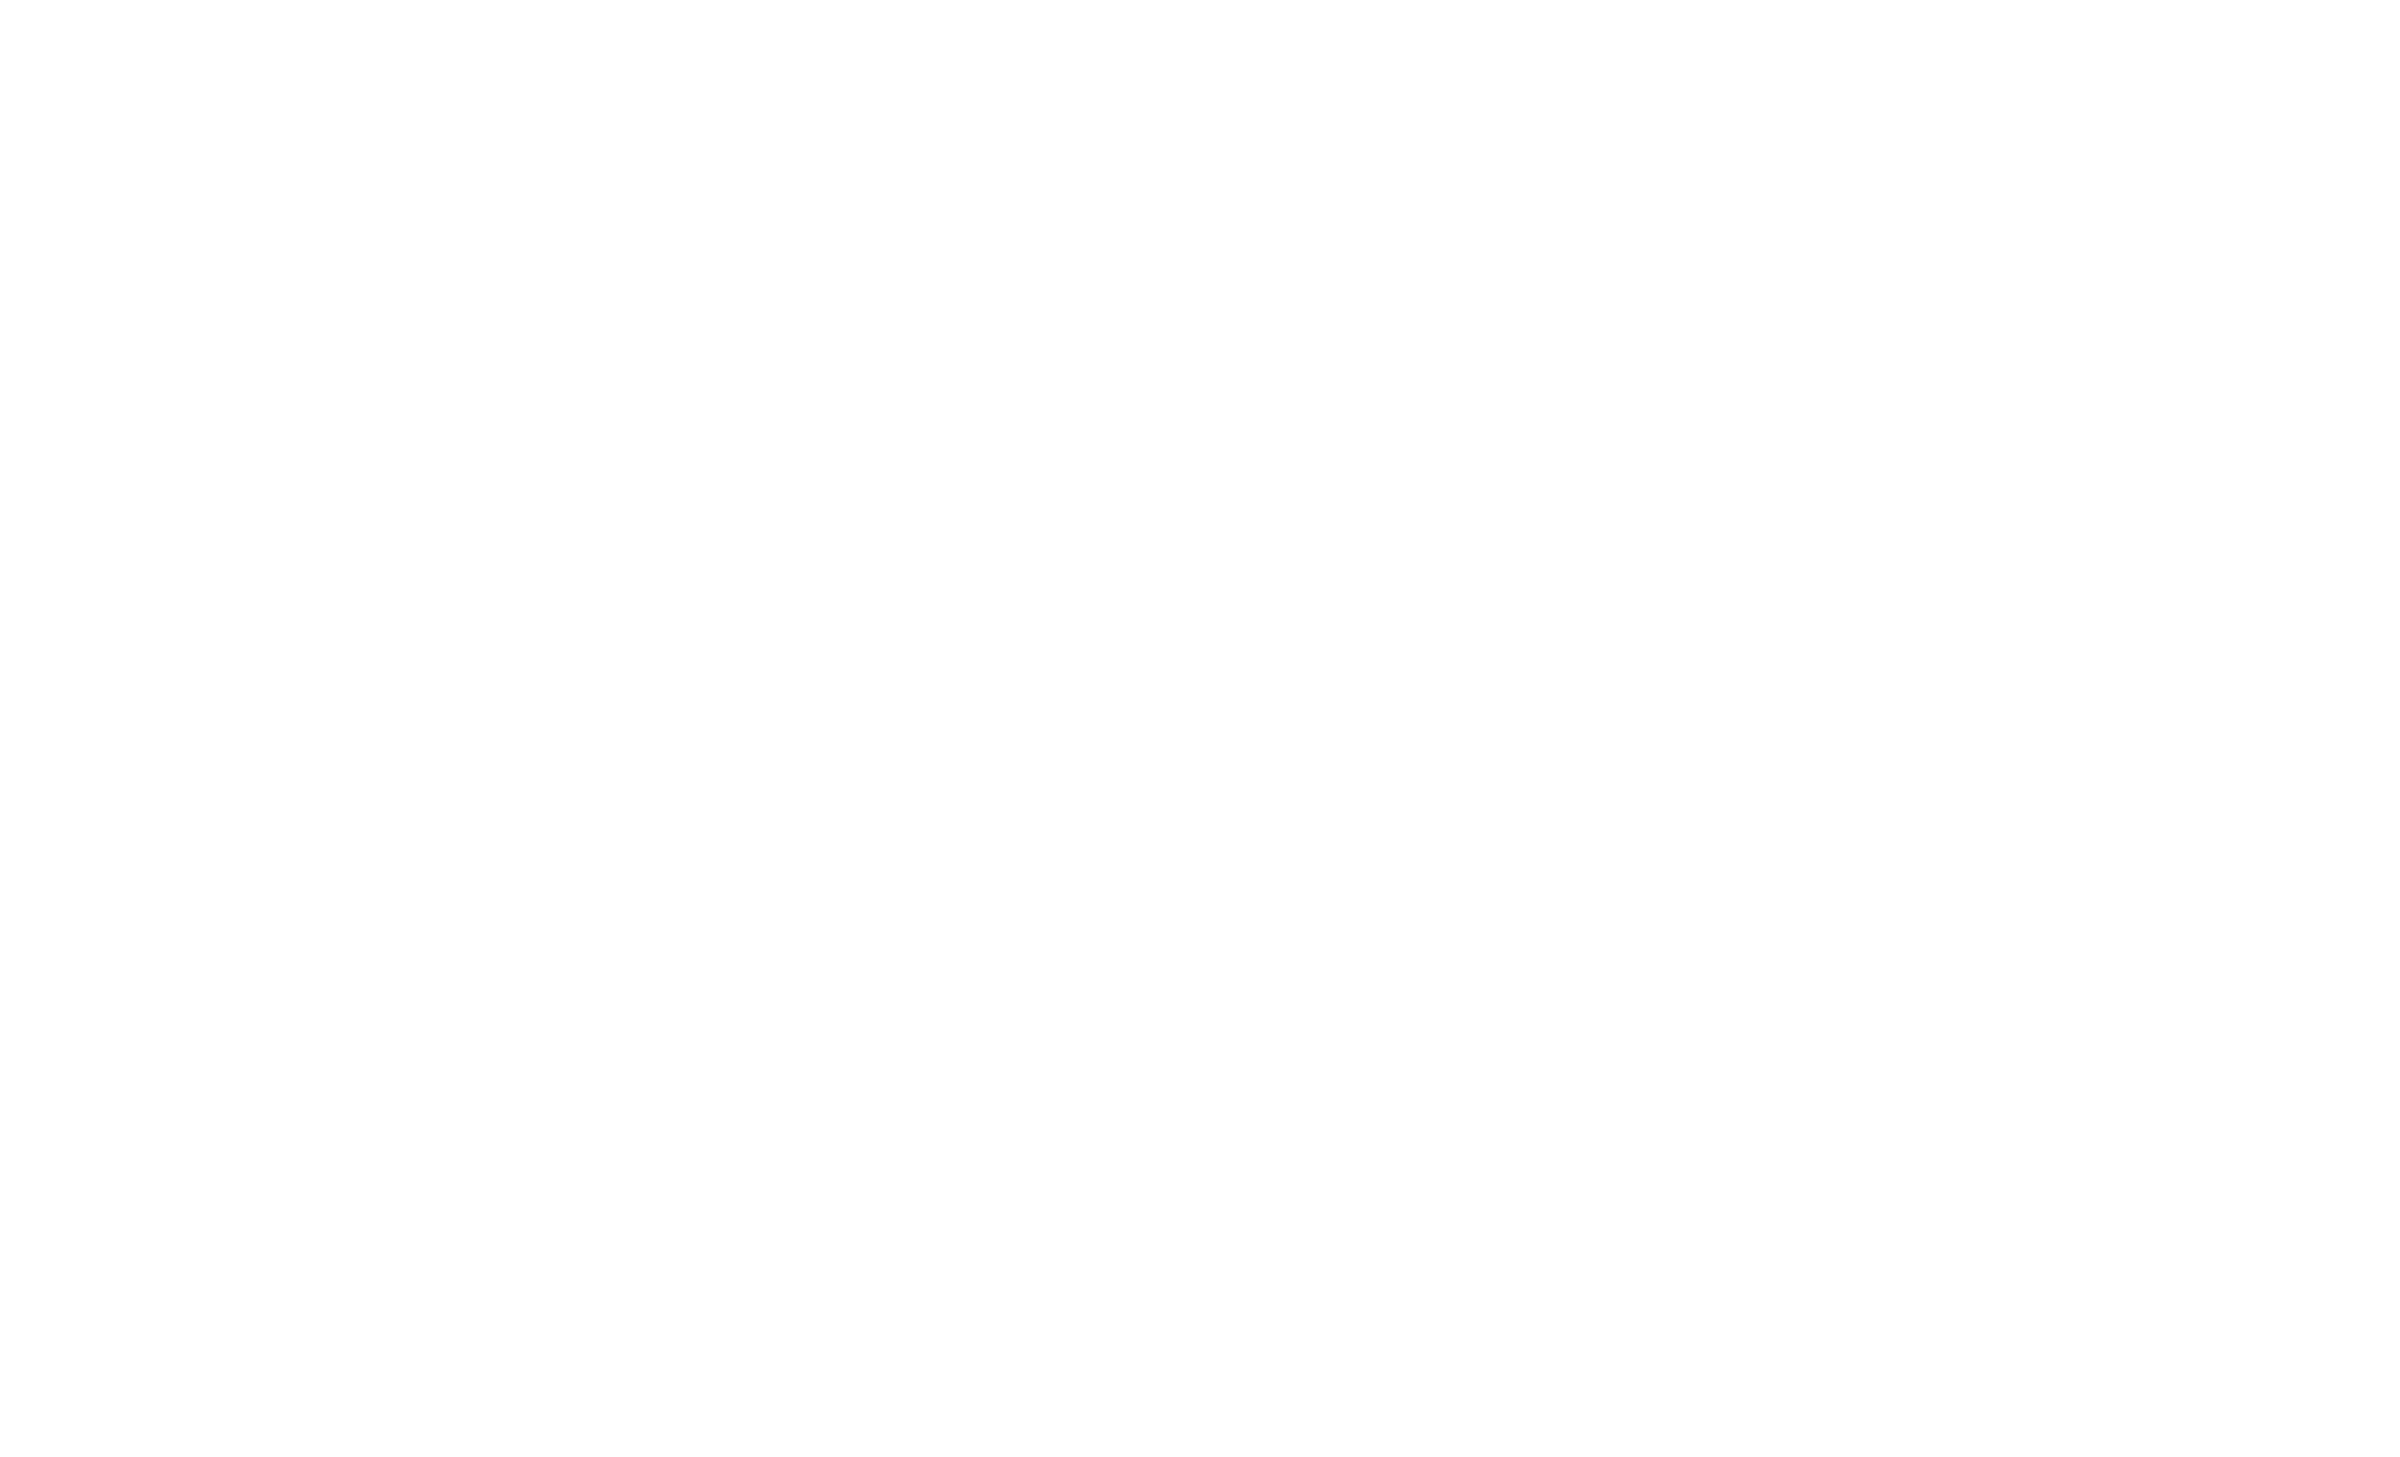

What Is an Impacted Wisdom Tooth?

An impacted wisdom tooth occurs when the tooth does not fully emerge from the gums due to lack of space.

Types of impaction include:

- Horizontal impaction

- Vertical impaction

- Partial eruption

- Fully impacted tooth

Impacted teeth can cause infection, pain, and damage to nearby teeth.